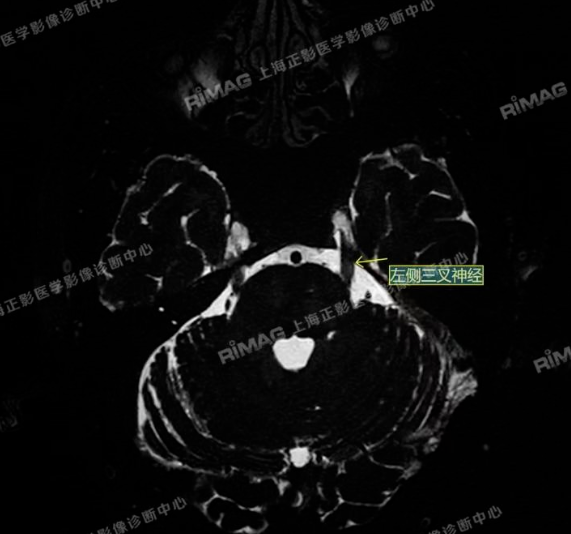

本例患者接受了MRTA(磁共振体层成像脑血管显影术)检查。这是一种非常精细的磁共振成像技术,能够清晰显示脑神经与周围血管的立体关系,尤其适用于三叉神经痛的病因诊断。

影像表现:右侧三叉神经根部外下方见小血管斜跨,与三叉神经分界不清;左侧未见明显异常(对照)。